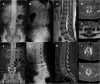

Figures